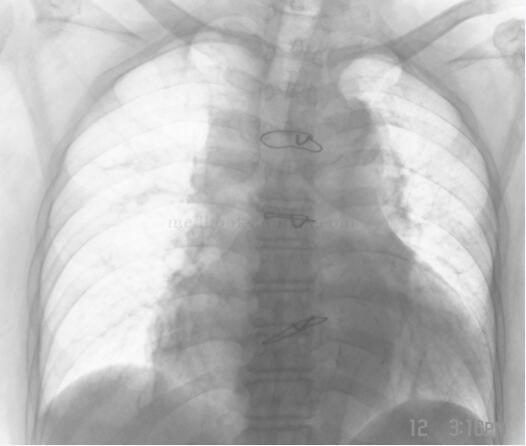

拔除电极及使用亚胺培南50天后患者再次发热,体温39℃以上,白细胞 22.4×109/L,中性粒细胞 95.1%。连续2次血培养出阴沟肠杆菌。心脏彩超提示心腔内电极上有赘生物。考虑发热仍与心腔内电极有关,转入心外科以开心取出电极。3日后手术顺利进行,将电极连同起搏器一并取出(图9-3-3),取出的电极及三尖瓣上均有串珠样赘生物附着,三尖瓣后瓣上赘生物培养出阴沟肠杆菌。

图9-3-3 开心手术后的胸部平片